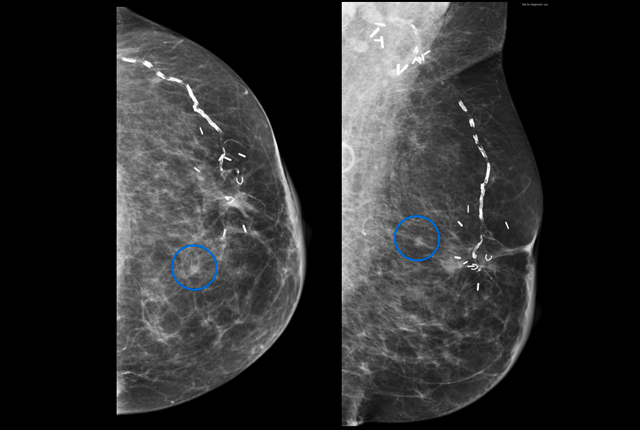

The rate of mammography use by breast cancer survivors has steadily declined since 2009, particularly among younger survivors, according findings published today in the Journal of the National Comprehensive Cancer Network.

The investigators reviewed a nationwide commercial claims database to review annual mammography rates in patients ages 40 to 64 years with a personal history of breast cancer diagnosis. For survivors between ages 50 and 64, they found approximately 74% were getting annual mammograms from 2004-2009, but the rate slipped to 67% by 2016. For the 40- to 49-year-old group, annual mammography rates held steady at 70% from 2004-2009 before dropping to 57% by 2016.

“Most people do quite well after completing their treatment for breast cancer, however some will have a recurrence of their prior cancer or develop a new breast cancer. Mammography is an important tool for detecting these cancers earlier, when they are smaller and more easily treated,” said lead researcher Dr. Kathryn P. Lowry, assistant professor of radiology at the University of Washington School of Medicine.

According to the results, annual mammography rates declined by approximately 1.5% per year from 2009-2016 overall, but that rate of decline jumped to 2.8% for survivors 40- to 49-years-old. The study authors note this is particularly concerning given that younger patients are more likely to develop aggressive tumors and also have a longer remaining life expectancy.